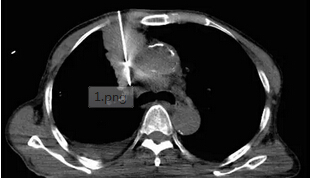

第二位患者已經(jīng)80多歲了,一直有慢性的肺心病,體檢發(fā)現(xiàn)了肺上一個(gè)3cm左右的腫塊,得知有局部消融這種微小創(chuàng)傷的治療手段,仿佛發(fā)現(xiàn)了救命稻草。

從上圖看患者肺部有嚴(yán)重的肺纖維化、肺大泡,肺功能很不好,左下肺還有一個(gè)3cm左右的腫塊

上圖:我們同樣在CT的引導(dǎo)下把消融針穿入腫瘤內(nèi)部,并獲取了部分腫瘤組織標(biāo)本用于病理定性檢查。